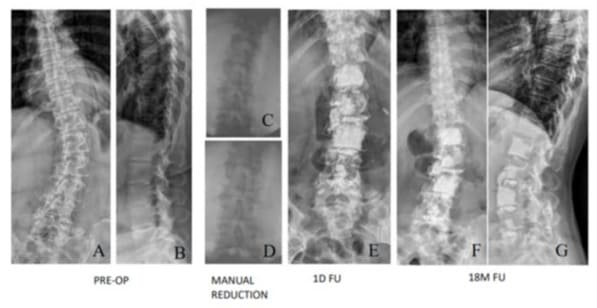

Degenerative Lumbar Scoliosis (DLS) may cause low back pain, leg pain, coronal imbalance and disability [1,2] and sometimes, surgery, including spinal decompression or fusion, is recommended. However, posterior instrumentation with bone grafts for the treatment of DLS is not only time consuming, but also has an elevated risk of complications [3,4]. The high incidence of operation complications leading to an advancement as an alternative treatment has launched in the past decade, i.e., Percutaneous Cement Discoplasty (PCD). This procedure was intended to decrease spinal instability for the advanced disc degeneration and promise clinical results with low complication rates have been reported [5-10]. PCD has been reported as an excellent target therapy for pain relief, but comparatively poor for spinal stenosis and scoliosis correction. PCD has no significant correction for lumbar lordosis or scoliosis and 14.7% of 156 PCD patients required second decompression surgery [5]. Due to osteoporosis in PCD elders, adjacent vertebral fractures may occur when scoliosis was corrected and increased stress in the vertebral bodies on the concave side (Figure 1).

Figure 1: A 68-year-old 32-kg female with degenerative scoliosis 70‘, thoracolumbar kyphosis 83’ (A, B) was treated with L3/5 open interbody cementation and L1/2, L2/3 cement discoplasties (C, D). An L2 compression fracture occurred one month later and caused re-kyphoscoliosis (E, F). L2 was reconstructed with one body cage with cementation and L3, L4 prophylactive vertebroplasties were done (G, H).